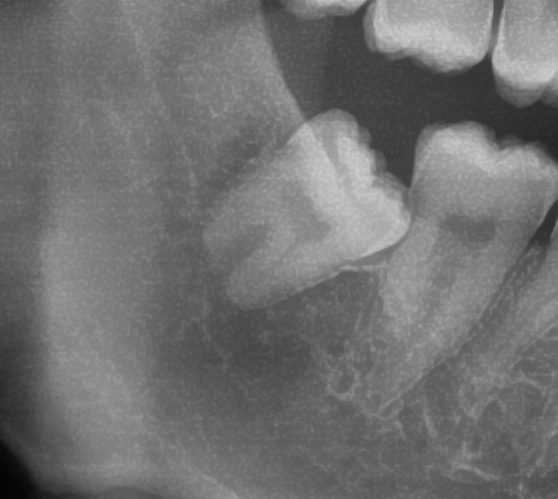

次にパノラマ写真を撮影してみると、右下の親知らずは手前の歯の歯を押すように少し斜めに生えているのが確認できました。